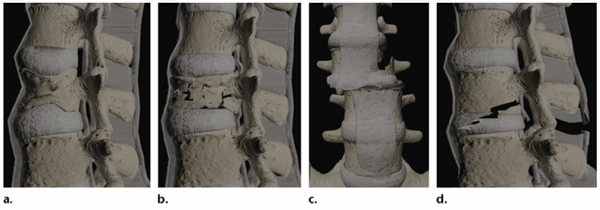

Классификация. Классификация переломов зуба аксиса, предложенная в 1974 г. Anderson и D'Alonzo, актуальна и в настоящее время. Основанная на морфологичес-ких нарушениях, эта классификация, тем не менее, позволяет судить и о механизмах травмы, и о методах лечения, и о прогнозе. Основываясь на дополнительных методах исследования, классификация продолжает совершенствоваться и развиваться. С появлением компьютерной томографии, спиральной компьютерной томографии стало возможным более точно проследить линию излома, направление смещения фрагментов. В классификациях Hadley, А.А. Луцика, Я.Л. Цивьяна имеются небольшие уточнения основных типов повреждений.

- I тип - отрыв (косой перелом) верхушки (апикальной части) зуба аксиса в месте прикрепления крыловидной связки (этот тип перелома зуба аксиса встречается крайне редко, поэтому в литературе описаны единичные случаи таких переломов; это повреждение - стабильное);

- II тип - линия излома при переломе проходит по «талии» зуба, т.е. перелом шейки в месте соединения зуба с телом аксиса (это повреждение является нестабильным); оскольчатые переломы основания зуба классифицированы как тип IIа (выделение этого подвида обусловлено сложностью лечения данного повреждения);

- III тип - линия излома распространяется в тело аксиса с переходом на верхнюю суставную фасетку, т.е. перелом у основания зуба в теле аксиса (при этом повреждении возникает флексионно-экстензионная нестабильность);